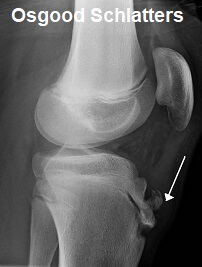

4. Osgood Schlatters Disease

Osgood Schlatter Disease is one of the most common causes of knee pain in teenagers, especially males.

Osgood schlatters Disease is on of the most common causes of knee pain in teenager

• Causes: Osgood Schlatters usually develops after a growth spurt due to the bones growing faster than the muscles, causing friction. This can lead to a bony lump forming just below the patella

• Symptoms: There is usually pain below the kneecap, worse with activity, better with rest.  Tenderness and swelling over the shin bone are common

• Treatment: A combination of PRICE, exercises, knee straps and knee pads usually work well

• Recovery: This is one of the longer lasting causes of knee pain and it can take anywhere from a few weeks to 2 years to settle